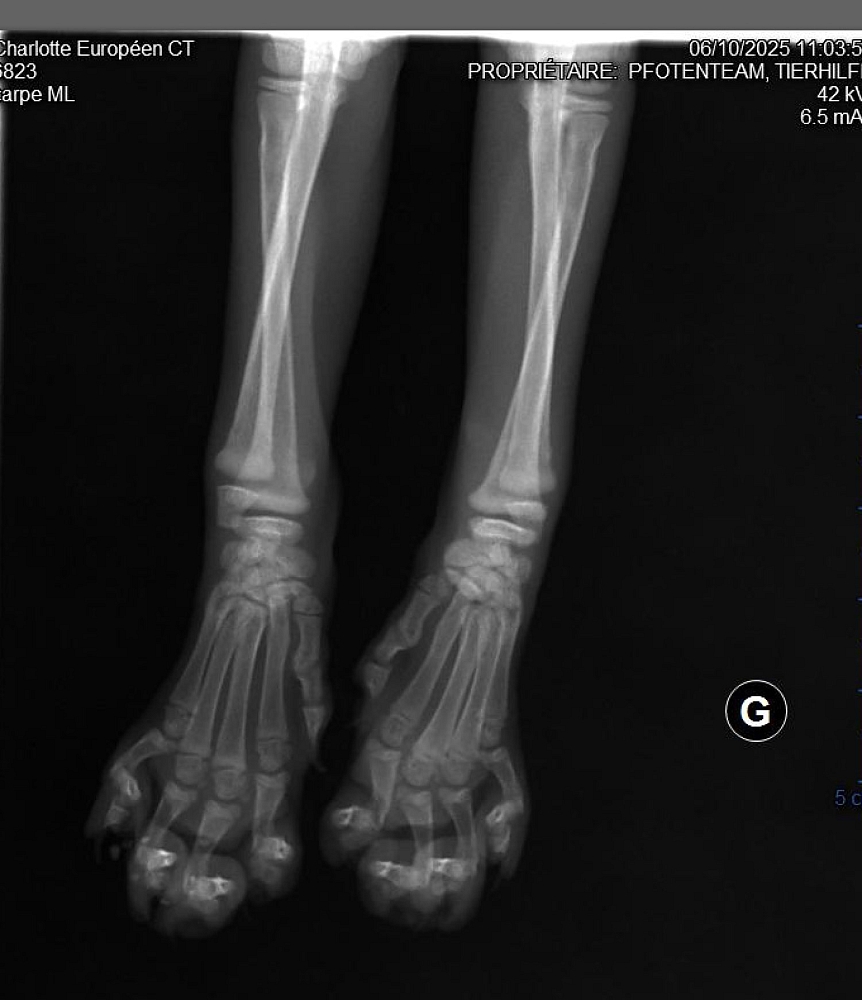

So  mussten beide einige Tage stationär in der Tierklinik an die Infusion, Charlotte hatte starkes Fieber, ihre Beine wurden geröntgt,  bei Dora hingegen setzte nach den Medikamenten eine Unterkühlung ein, sie musste auf die Wärmematte. Beide bekamen Antibiotika und es wurde ein Bluttest gemacht, die Ärztin vermutete einen akuten Calicivirusschub.